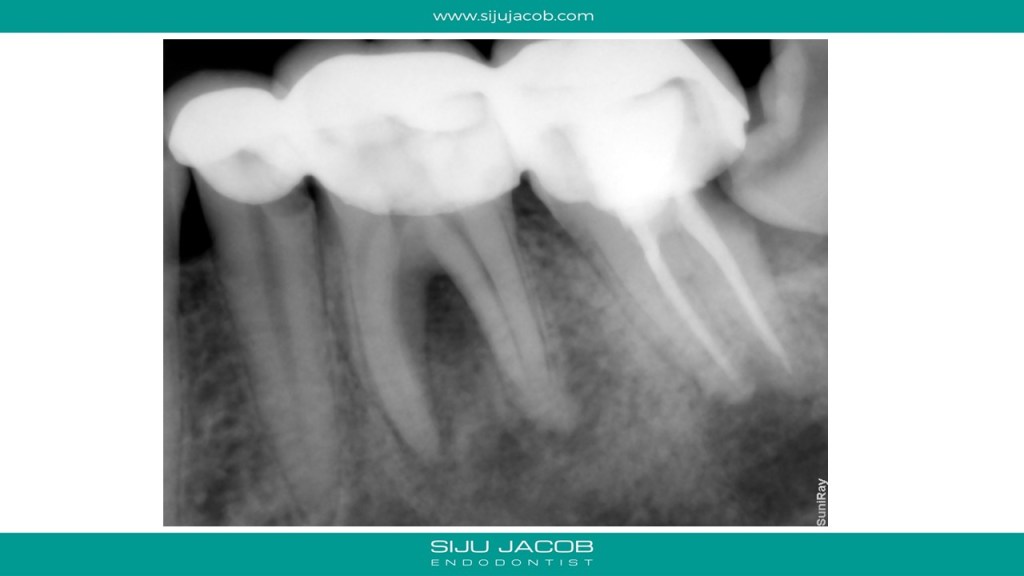

This patient came with a small swelling in relation to the first molar and carious premolar. The molar was non vital and had furcal bone loss. Most cases like these with furcal bone loss associated with a non-vital tooth usually heal with endo alone. In this particular case, I had noticed that the mandibular second molar had secondary decay under the crown and a large peri-apical lesion. I had advised extraction of the wisdom tooth and the mandibular second molar. To my surprise, the patient came back after a year with pain in relation to the second molar. I saw that the clinician had put a crown on that! I advised extraction of the second molar again. 🙂